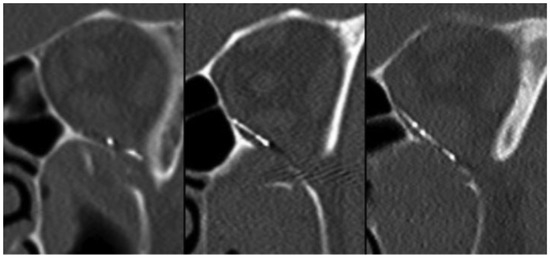

Frontal Sinus Fractures: Management and Complications

by Xi Lin Jing and Edward Luce

Craniomaxillofac. Trauma Reconstr. 2019, 12(3), 241-247; https://doi.org/10.1055/s-0038-1675560 - 19 Feb 2019

Cited by 30 | Viewed by 831

Frontal sinus fractures are relatively rare maxillofacial injuries (only 5–15% of all facial fractures). The appropriate management of frontal sinus fracture and associated pathology is controversial. Diagnosis and treatment of frontal sinus fractures has improved with the advances of high-resolution computed tomography technology. [...] Read more.

Frontal sinus fractures are relatively rare maxillofacial injuries (only 5–15% of all facial fractures). The appropriate management of frontal sinus fracture and associated pathology is controversial. Diagnosis and treatment of frontal sinus fractures has improved with the advances of high-resolution computed tomography technology. Treatment of frontal sinus fractures depends on several factors, including contour deformity of anterior table; the presence of CSF leak or air–fluid level in the sinus, likelihood of nasofrontal duct obstruction, and degree of displacement of posterior table. Nasofrontal duct patency should be checked if fracture pattern is highly suspicious of ductal injury. Cranialization is performed in cases of severely comminuted posterior wall fracture. Long-term complication of frontal sinus fracture can occur up to 10 years after initial injury or intervention; so, judicious long-term follow-up is warranted. This article presents the management and complications of frontal sinus fractures. Full article